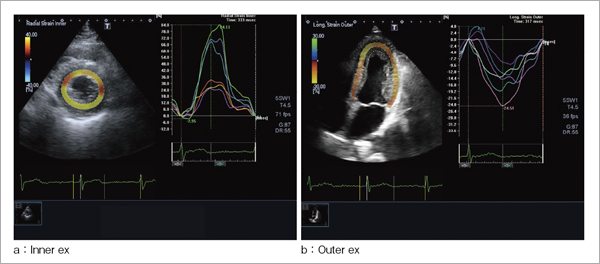

2D WMTの基本となる技術は,動きを検出するためのパターンマッチング処理を超音波動画像に応用したものである。Transmural Trackingでは,2次元空間での情報を最大限に活用することで,心筋内での動き検出精度を高める工夫を行った。また2D WMTでは,基準とするフレームでストレインを計算する方向に2点のペアが設定されるが,このペアが連続する画像中でどのように動いたかをスペックルトラッキングの手法により追跡して求め,定義した方向の距離変化成分を抽出し,基準フレームでのペア間の距離で規格化することにより,ストレインを求める。Transmural Trackingでは,内外膜以外に中層位置も有しているので,図1に示すように,壁厚方向(Radial,Transverse)では内膜側のInner,外膜側のOuterおよび全壁厚のTotalの3種類を定義できる。同様に,接線方向(Circumferential,LongitudinalおよびRotation)では,内膜上のInner,外膜上のOuterおよび中層上のMidの3種類を定義できる。こうした各種ストレインやローテーションの値はカラーコード化され,図2のように,パラメトリックイメージングとして心筋に重畳して表示することが可能である。

図2 Transmural Trackingのパラメトリックイメージング